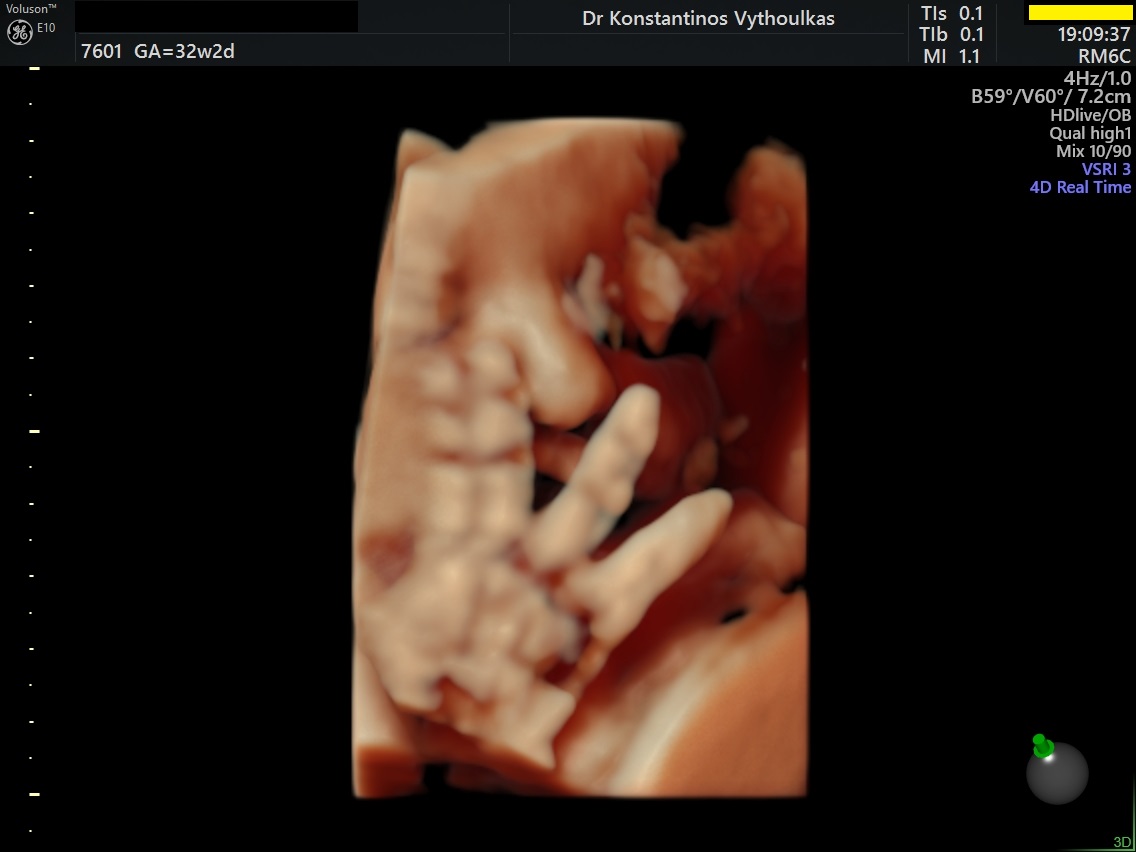

Φωτογραφίες από το αρχείο και από το χώρο του ιατρείου του γυναικολόγου Βυθούλκα Κωνσταντίνου, καθώς και του εργαστηρίου της κυτταρολόγου Λιβέρη Κατερίνας.